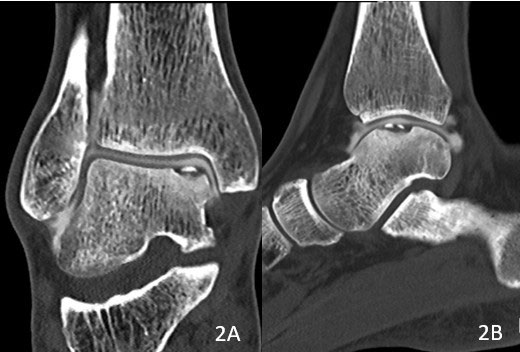

Bild: Universitätsklinik Balgrist

Bei vorliegender osteochondraler Läsion kann mittels CT-Arthrographie (CT-Untersuchung mit vorheriger Kontrastmittelinjektion) das Ausmass des Knochendefekts und die Stabilität der darüberliegenden Knorpeloberfläche noch genauer untersucht werden.